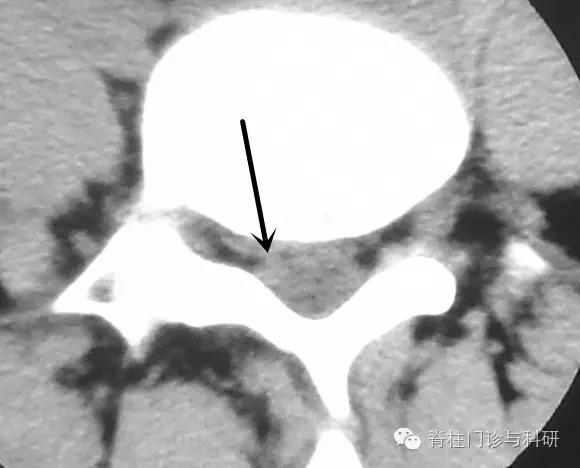

下图这类患者,属于形态不规则、游离的部分髓核在侧隐窝和神经根处于若即若离的状态。该患者突出物的CT值较高,虽然突出物总体形态有些偏大,但仍然有临床症状“自愈”的可能。